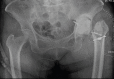

Case report: We present this challenging and unique case of a 64-year-old female patient where the acetabular component screw was found to be adherent to the external iliac vessels, with vascular injury imminent. During revision surgery, the iliac vessels were first released free of all adhesions with the intrapelvis screw using an ilioinguinal incision and retroperitoneal approach. The prosthesis was removed using a posterior approach to the hip joint. Definitive surgery was performed after 2 weeks.